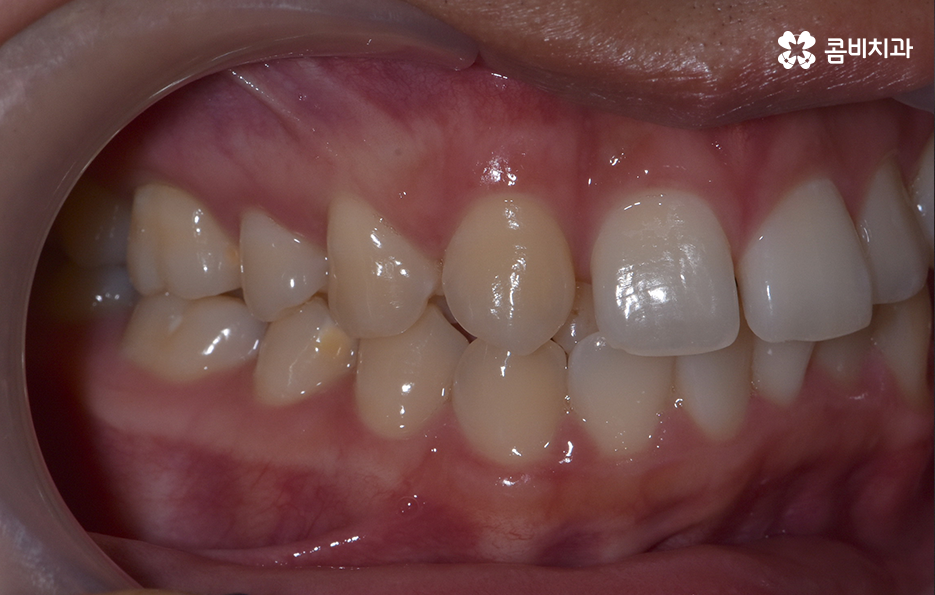

덧니 교정 사례를 살펴보면 치열을 가지런하게 재배열 하는 기준만으로 보면 비발치로도 충분히 교정이 가능한 경우도 많지만 돌출입의 개선이나 입술라인 등을 고려해서 발치교정을 하게 되는 사례도 많이 있어요

치아교정의 결과에 있어서 단지 정면에서 바라보는 치열이 가지런하게 보이는 것이 아니라 얼굴형과 잘어울리는 조화로운 결과 또한 무척이나 중요하기 때문에 치아교정 후의 얼굴변화를 잘 예측하는 것이 발치교정을 판단하는데 중요한 판단 기준이 될 수 있는데요

치아교정은 한 번 시작하면 장기간의 치료 기간도 고려해야 하고 치료 후 결과를 평생 유지한다는 점에서도 치료 후 결과에 있어서 얼굴형과의 조화를 잘 예측하는 것이 무척이나 중요한 단계라고 볼 수 있어요. 따라서 치료 목표를 세우는데 있어서 무분별하고 불필요한 발치교정은 옥니와 같은 부작용이 발생될 수 있다는 점에서 주의해야 하겠지만 당장 발치가 두려워서 비발치 교정만을 고수하는 것도 얼굴변화에 대한 아쉬움으로 재교정을 고려하는 사례도 있다는 점을 주의하여 나에게 적합한 치료 계획을 의사와 잘 상의하시길 바라고 있어요